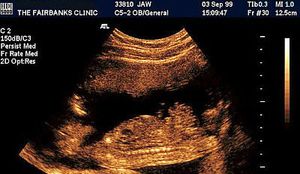

Amniotic band syndrome is very rare and has poor outcomes. Obstetric ultrasound can identify potential anatomic abnormalities.